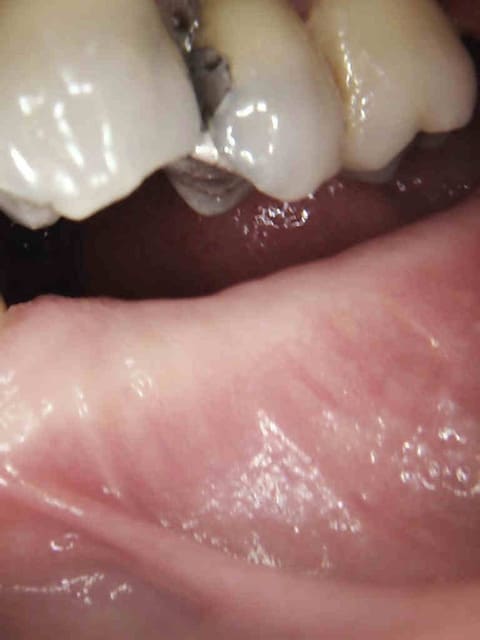

3 ezcjhg - Eugenol

4 w0fyb0 - Eugenol

5 hb1jpv - Eugenol

6 qrlsxe - Eugenol

7 g5aq0k - Eugenol

8 cyv9ae - Eugenol

9 kvtqqw - Eugenol

20/01/2015 à 14h09

@chicot

les endos sont chouettes.

je suis encore pour ma part pas mal long quand il s'agit d'endo.

sinon c'est quoi le truc entre la 5 et la 6.

Wed jet. Ca se pose avec une pince.